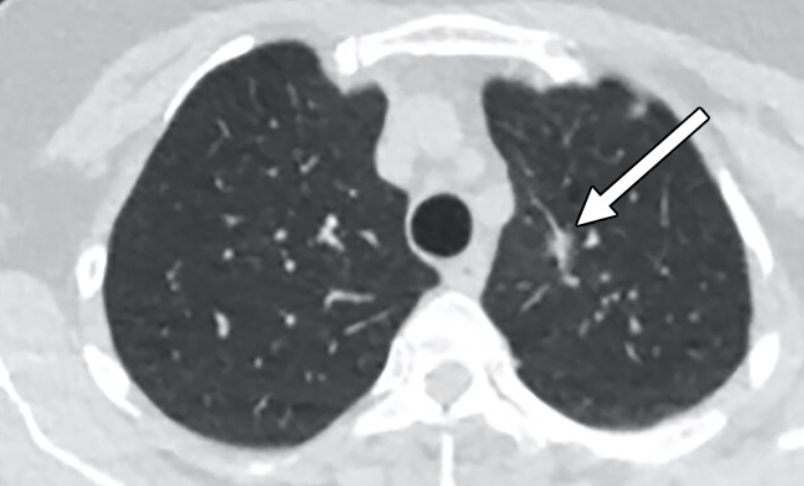

폐 편평세포암은 폐암의 한 유형으로, 주로 흡연과 관련이 있습니다. 기침이 3주 이상 지속되거나 피 섞인 가래, 숨이 차는 증상이 있으면 검사를 받아야 합니다. 흡연자는 비흡연자보다 편평세포암 발생 위험이 몇 배나 높습니다. 금연은 가장 강력한 예방책이며, 폐 건강을 지키는 가장 직접적인 방법입니다.

진단은 흉부 X선, CT, 기관지 내시경, 조직검사로 이뤄집니다. 치료는 수술, 방사선, 항암치료, 면역치료가 병합됩니다. 최근에는 맞춤형 치료제가 도입되어 생존율이 향상되고 있습니다.